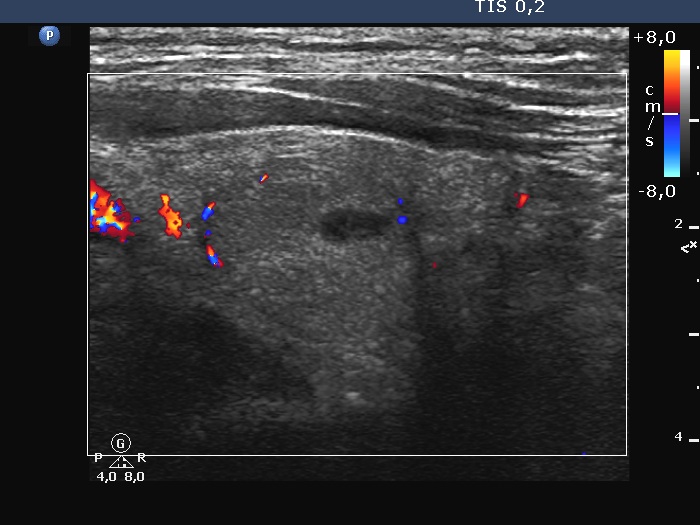

Left lobe, longitudinal scan, color Doppler mode. The lesion shows signs of perinodular vascularity.